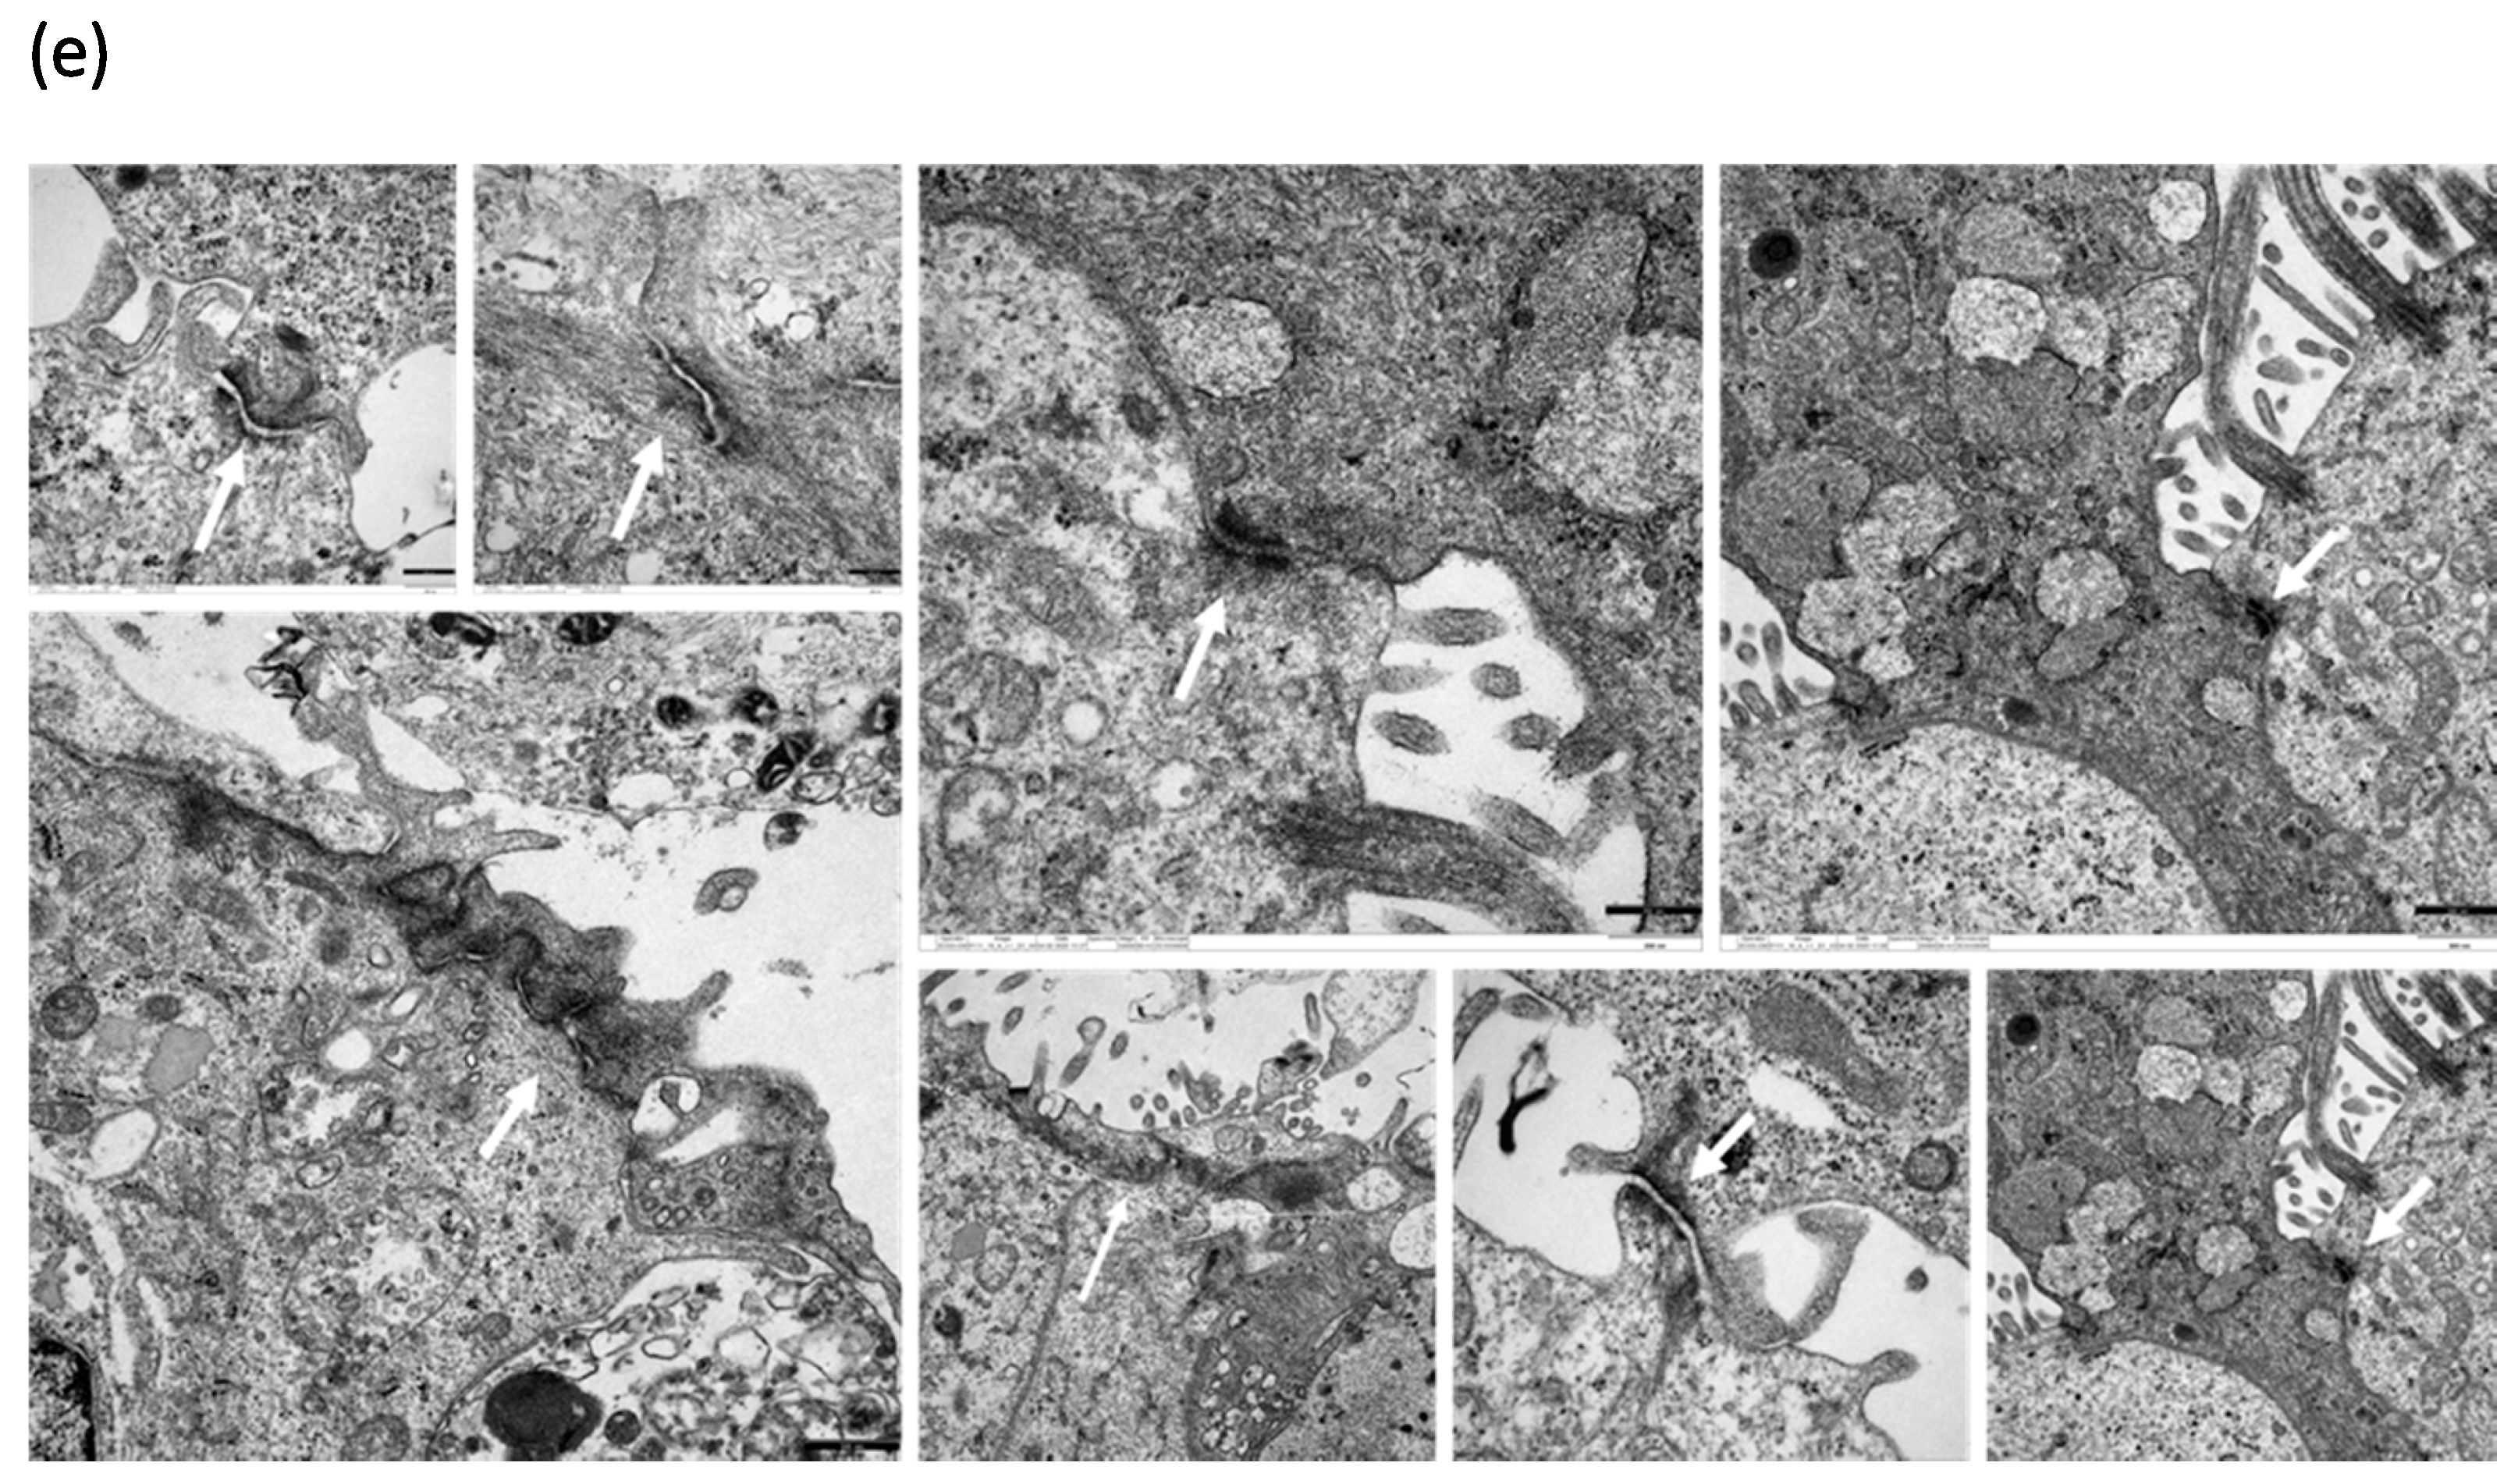

2.2.4. Transmission Electron Microscopic (TEM) Imaging of Organotypic 3D NAEPCs Cultures

3.4. HDM Increased the Permeability between Cell–Cell Contacts through Affecting the Epithelial Barrier Integrity